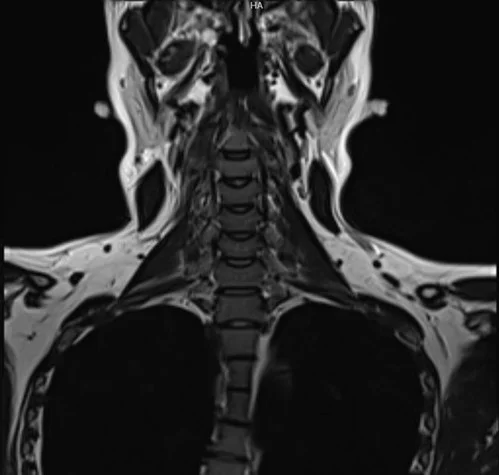

RESONANCIA MAGNÉTICA DE CERVICAL

La resonancia cervical, a diferencia de otros exámenes de imagenología, no utiliza radiación y ofrece una visión más completa de los tejidos blandos, como los huesos, ligamentos, tendones, músculos, discos intervertebrales y médula espinal.

La resonancia magnética cervical permite diagnosticar diversas patologías que afectan a la parte cervical de la columna vertebral, tales como tumores, sangrado, hinchazón, infecciones o inflamación en la zona.

¿Qué es una resonancia magnética cervical? Es un examen de diagnóstico por imagen que utiliza un campo magnético fuerte, ondas de radio y tecnología computarizada para obtener imágenes detalladas de los elementos óseos y ligamentos de la columna cervical, así como de los tejidos blandos vecinos.

Una resonancia magnética cervical es un procedimiento crucial para identificar una variedad de afecciones en el cuello y la parte superior de la espalda. Gracias a su tecnología, puede revelar problemas en los tejidos blandos dentro de la columna vertebral, como la médula espinal, los nervios y los discos intervertebrales. Lo que ayuda a los médicos a planificar el tratamiento más adecuado para las condiciones detectadas.